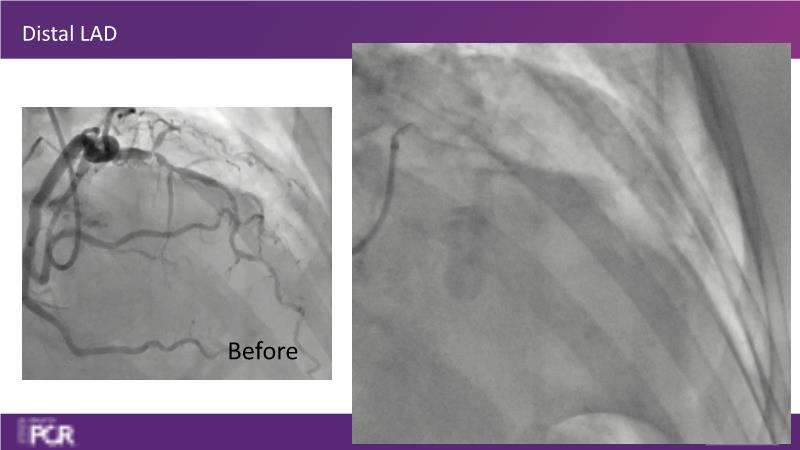

Through the study of two cases, this session examines the need for stenting bifurcation lesions and the role of DEB technology in avoiding stent-related complications in long diffuse disease. It emphasizes the benefits of SELUTION SLR balloons for de novo lesions, discussing how sustained limus release technology can broaden DEB indications and reduce metal usage, understanding the limitations of DES and the emerging role of DEB with sustained limus release, and learning how to identify dissections that can be left unstented.